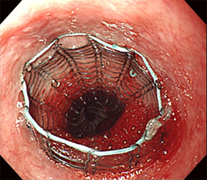

癌によって狭くなった消化管に金属製の「拡がるバネ」を入れ、食べ物の通りを出来る限り良くします。癌を根治させることは出来ませんが、進行癌の患者さんに、食べる喜び、便通を取り戻して頂く処置です。